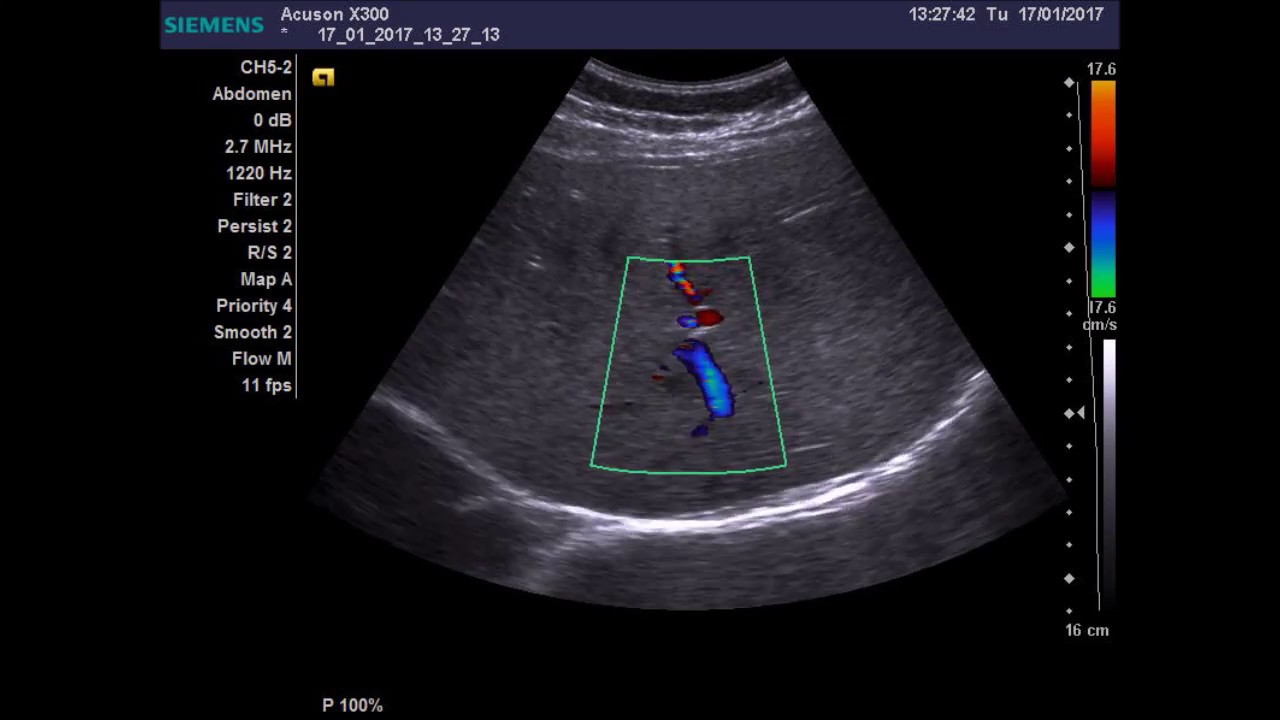

В нормальном состоянии печень представляет собой однородную структуру, ткань имеет среднюю плотность. На УЗИ видна масса серого цвета, поделенная на доли. В ней выделяют гипоэхогенные и гиперэхогенные участки, которые лучше видны в местах прохождения сосудов и связок. Если структура органа теряет однородность, врач может определить наличие заболевания.

Объемное изображение, получаемое в результате обработки, представляет собой черно-белую картинку, на которой гиперэхогенные участки имеют светлый оттенок. Кости, жировая ткань, опухоли, стенки крупных сосудов имеют почти полностью белый цвет.

- Гиперваскулярные образования печени имеют повышенную эхоплотность: они лучше отражают ультразвуковые волны, чем прочие ткани. Подобные участки на мониторе ультразвукового исследования представляют собой белые пятна, изоэхогенные образования, представляющие собой железистые ткани, — серыми.

- К гипоэхогенным относят участки, которые плохо отражаются на УЗИ: анэхогенные зоны состоят из воздуха и жидкостей, поэтому слабо отражают волны.

Выделяют диффузные эхогенные образования. Они показывают воспалительные процессы, а очаговые образования в этом случае свидетельствуют о наличии кисты, абсцесса. Крупные сосуды также напоминают гипоэхогенные участки, что связано с плотной оболочкой сосудов. Если происходят очаговые изменения, вероятнее всего, появилось новообразование неизвестного качества или произошло изменение кисты.

По этиологии поражения печени делят на доброкачественные и злокачественные. Для них имеется специальный показатель, который называют васкуляризацией. Он отображает уровень доброкачественности, поэтому злокачественные называют гиперваскулярными, а доброкачественные — гиповаскулярными или гиподенсивными.

Абсцесс печени возникает при бактериальном заражении организма. Возникшие при этом патогенные микробы проникают в область печени (обычно в правую ее часть). На ранней стадии заражения на УЗИ видно, что это гиповаскулярное образование, которое приводит к гибели здоровых клеток.